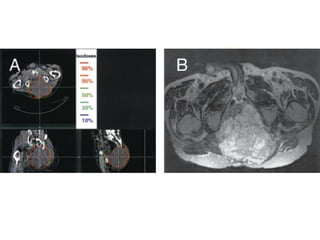

Three-dimensional conformal radiation techniques using multiple fields, multileaf collimation, and intensity-modulated IMRT beams are useful aids to optimize the homogeneity of the dose within the target volume while sparing adjacent normal structures allowing treatment of previously inaccessible areas. Techniques of radiation delivery

IMRT